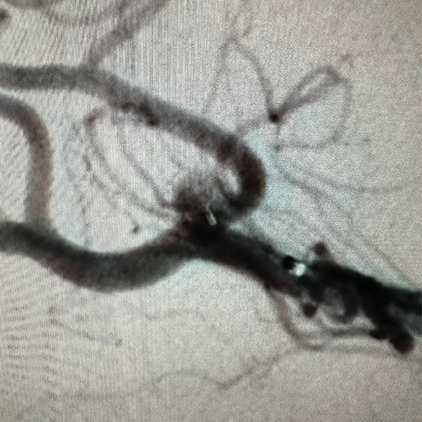

We provide devices and treatment of complex brain aneurysms and vascular malformations free of cost. These are some of the complex brain aneurysm we have recently treated in Pakistan. Devices and catheters used for all procedures were provided by Pakistan Stroke Initiative, and in some cases charges for hospitalization as well.

One of the key components of our stroke center is the Neuroangiography biplane suite. This advanced imaging system enables precise diagnosis and treatment of stroke and brain aneurysms. However, the cost of this technology is substantial, with a single biplane suite costing millions of dollars. Your support will directly contribute to acquiring this life-saving technology and ensuring better stroke treatment for thousands.

Pakistan Stroke Society played a key role in the development of the Mechanical Thrombectomy Program at the National Institute of Cardiovascular Diseases (NICVD) - a groundbreaking step in offering life-saving stroke interventions within critical time windows.

Pakistan Stroke Initiative Society played a key role in the development of the Mechanical Thrombectomy Program at the National Institute of Cardiovascular Diseases (NICVD) – a groundbreaking step in offering life-saving stroke interventions within critical time windows.